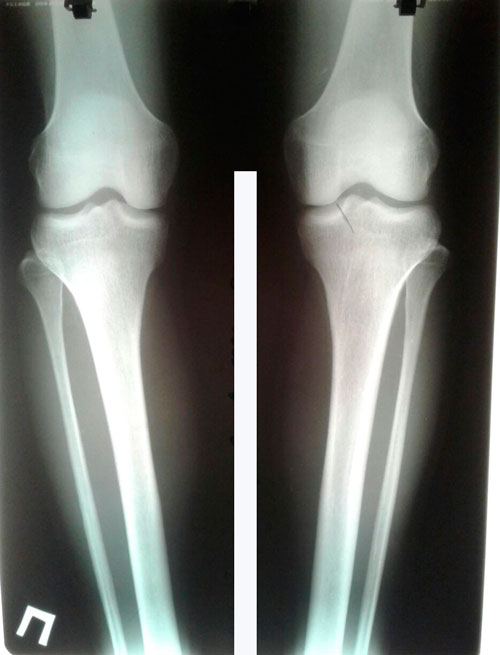

Исходник - 23 года.

Дата операции 29.04.2017г.

P.S. Н.Н. уже давно не попадались такие КРЕПКИЕ кости!